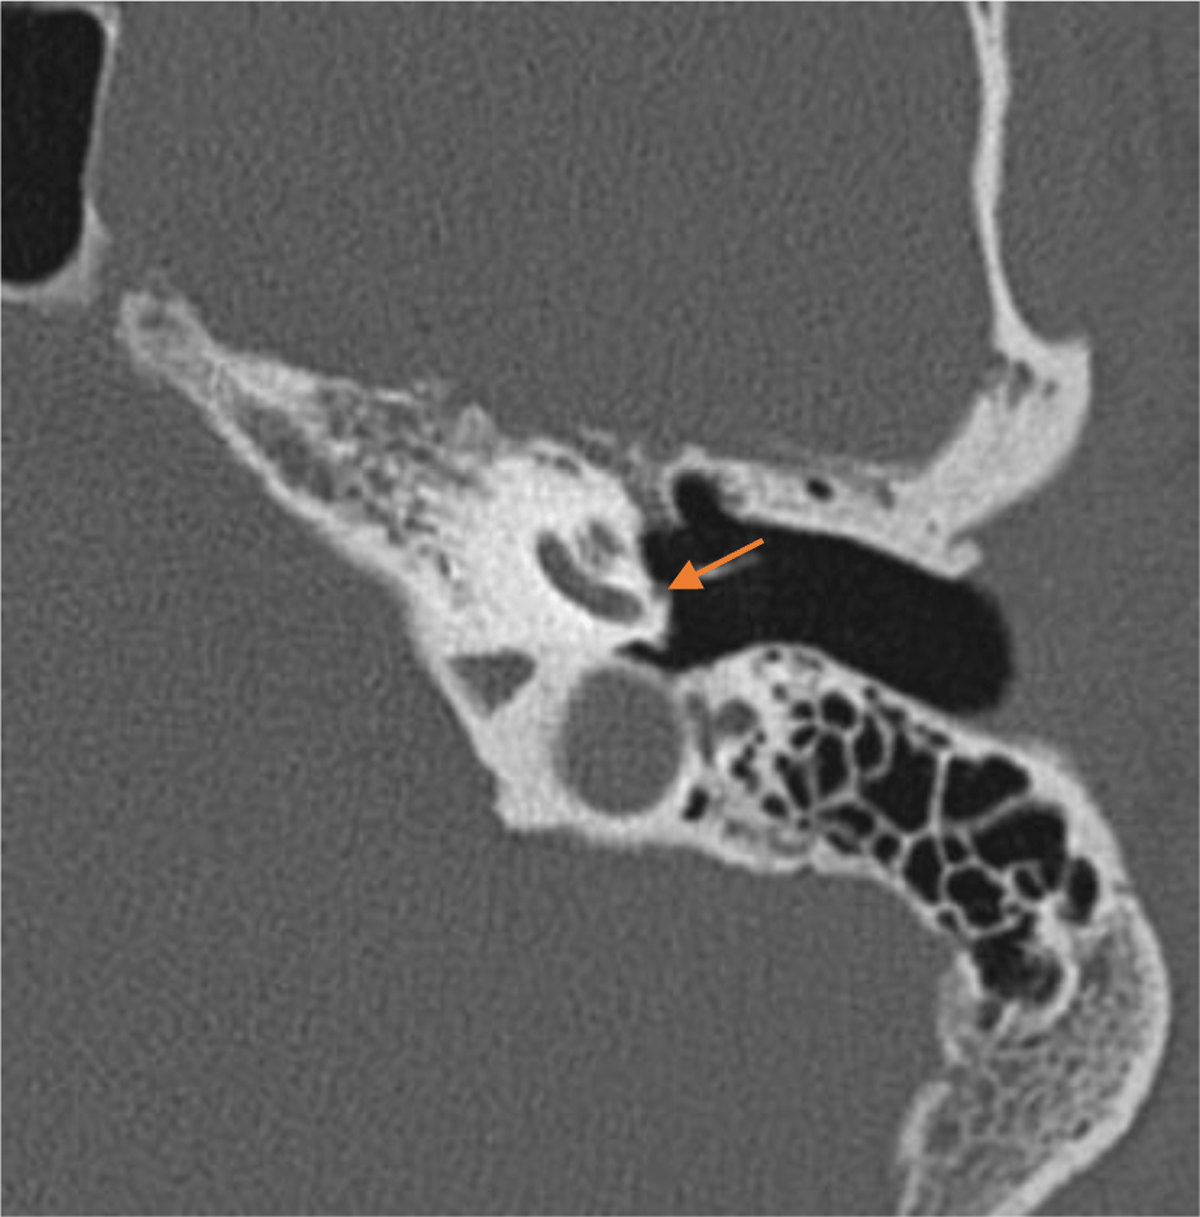

Figure 2

Axial CT scan showing the PSA on the cochlear promontory.